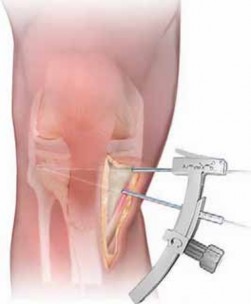

PLATE FIXATION

1. The handle of the osteotomy wedge can be removed (

TECH FIG 5A

), leaving the anterior and posterior tines in place.

1. The proper-sized osteotomy plate is then inserted into the osteotomy site (

TECH FIG 5B

). To respect the geometry of the tibial slope, it is recommended that the wedge in the plate be sloped from posterior to anterior.

2. The use of second-generation locking plates is recommended.

3. Before fixation of the plate, the tines are removed from the osteotomy wedge (

TECH FIG 5C

).

2. The plate is secured with two 6.5-mm fully threaded cancellous screws in the proximal fragment. (It is not necessary to use bicortical screws.) The distal fragment is secured with two 4.5-mm bicortical screws.

TECH FIG 5 • A. The handle of the osteotomy wedge is removed, and the wedge trial is placed between the tines to confirm the size of the osteotomy plate to be used.

TECHNIQUES TECH FIG 5 •

(continued)

B. The osteotomy plate is trialed. In this case, the posterior tine is in place and the anterior tine has been removed. C. Second-gener-ation locking plate in place. The white arrow points to the mark on the plate verifying the slope from anterior to posterior (ie, the trapezoid is larger posterior B C than anterior). BONE GRAFTING 1. Depending on the preference of the surgeon and patient, the osteotomy must be packed with bone graft and the medial cortical margins reinforced with tricortical iliac crest graft.